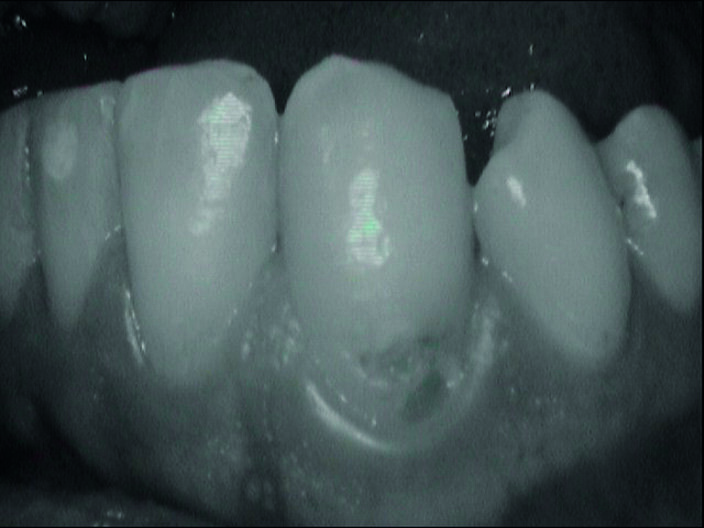

Durante l’esame obiettivo (Figg. 1a, 1b) rileviamo il danno iatrogeno da terapia ortodontica precedente alla visita e riscontriamo la presenza di processo carioso ICDAS 3 in zona 33 e in zona 47, white spots in zona 31 e 41. Durante l’esame obiettivo, l’ausilio della videocamera intraorale Sopro-Care (Acteon) permette, tramite filtri appositi, di evidenziare in modo rapido e accurato le zone di demineralizzazione e le aree infiammate e di mostrarle al paziente in real time, rendendolo attivamente partecipe e consapevole della situazione clinica (Figg. 2a-2f). I ricercatori del Baylor College of Dentistry hanno dimostrato che il 23,4% dei pazienti ha sviluppato almeno una white spot lesion durante il trattamento ortodontico.

Per procedere con il passaggio successivo è necessario ottenere un ambiente asciutto. Per questo la lesione cariosa viene asciugata con Icon-Dry (etanolo) e con un getto di aria (Fig. 10). Abbiamo applicato la resina Icon Infiltrante e la abbiamo lasciato agire per 3 minuti. Si può ripetere la mordenzatura più volte su una superficie di spessore consistente. Inoltre, se la decolorazione bianca scompare nel giro di qualche secondo dopo l’applicazione dell’etanolo (Icon Dry), la mordenzatura sarà sufficiente, altrimenti la mordenzatura dovrà essere ripetuta, fino a 3 applicazioni di acido da 2 minuti. L’infiltrante, estremamente fluido, penetra in profondità nello smalto per azione capillare e riempie la lesione (Fig. 11). Alla fine viene fotopolimerizzato.